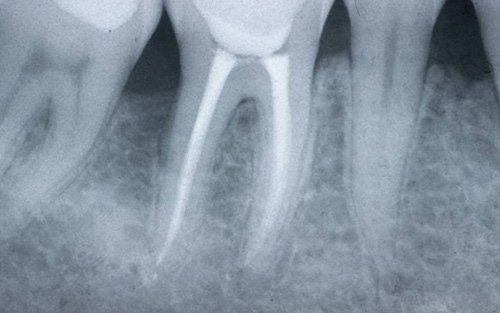

This treatment should be reserved for teeth that have irreversible pulp pathology (the nerve of the tooth) or an infection of the dental canals that has caused an abscess (acute apical periodontitis) or a granuloma (chronic apical periodontitis). While in the first two cases the tooth is very painful and the patient immediately seeks the dentist, the case of the chronic form is often silent, and therefore the patient may not notice anything for a medium to long period of time. In such conditions, it is only an X-ray image, taken during routine check-ups, that detects its presence. Root canal therapy can be completed by placing a latest-generation post inside the canal, as a means of retaining the material used for the reconstruction of the tooth. It will be up to the clinician to decide whether or not the restoration requires this additional anchoring system.